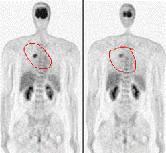

近日,中央电视台《新闻联播》、《科技之光》等栏目,报道了细胞免疫疗法在肿瘤治疗上的获得重大突破。一时间,细胞免疫疗法成为人们关注的焦点。人们很好奇:细胞免疫疗法究竟是种什么疗法?早期肿瘤真的可以治愈吗? [详细]

解放军三O七医院CTC肿瘤生物治疗中心(以下简称中心)自1997年就开始从事肿瘤的免疫治疗,是获得中国人民解放军总后卫生部批准、具有合法资质开展肿瘤细胞与基因治疗的临床科室,拥有1600平方米并通过GMP认证的标准GMP实验室,也是全军的肿瘤治疗中心。